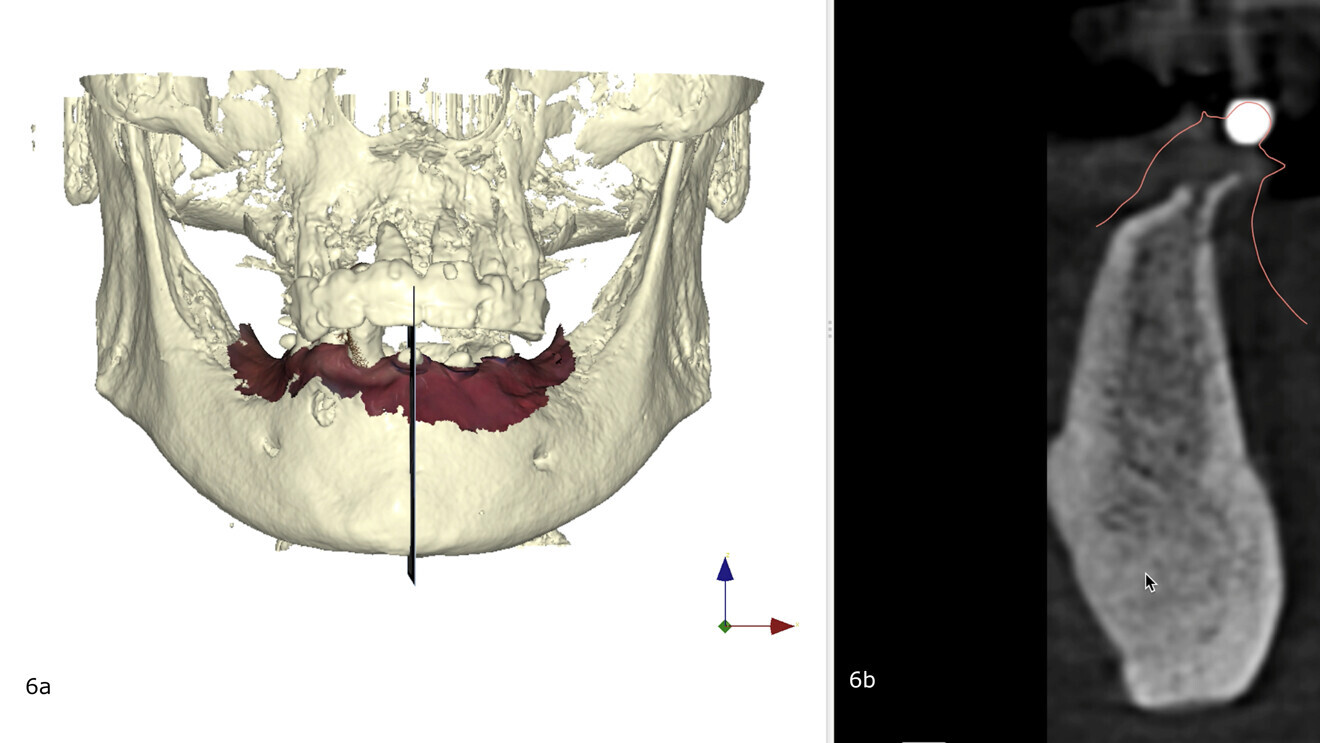

La combinaison des données DICOM et STL dans le cadre de l’édenté complet ou subtotal est rendu compliquée par le manque de repères fiables et fixes. L’astuce, ici, est de coller des autocollants avec des billes radio-opaques (www.suremark.com). Ces billes seront identifiées tant au niveau de la radiologie par leur opacité que sur l’empreinte optique par leur volume. La combinaison des données est alors facilitée (Fig. 5). Lors de la planification du traitement implantaire, le logiciel DTX Studio Implant a été utilisé (Fig. 6). Il a été décidé de placer quatre implants.

Figs. 6a et b : Planning implantaire (logiciel DTX Studio Implant) : quatre implants ont été planifiés. (a) La vue vestibulo- linguale met en évidence l’intérêt des billes radio-opaques sur les autocollants pour la bonne combinaison des (b) données DICOM et STL.